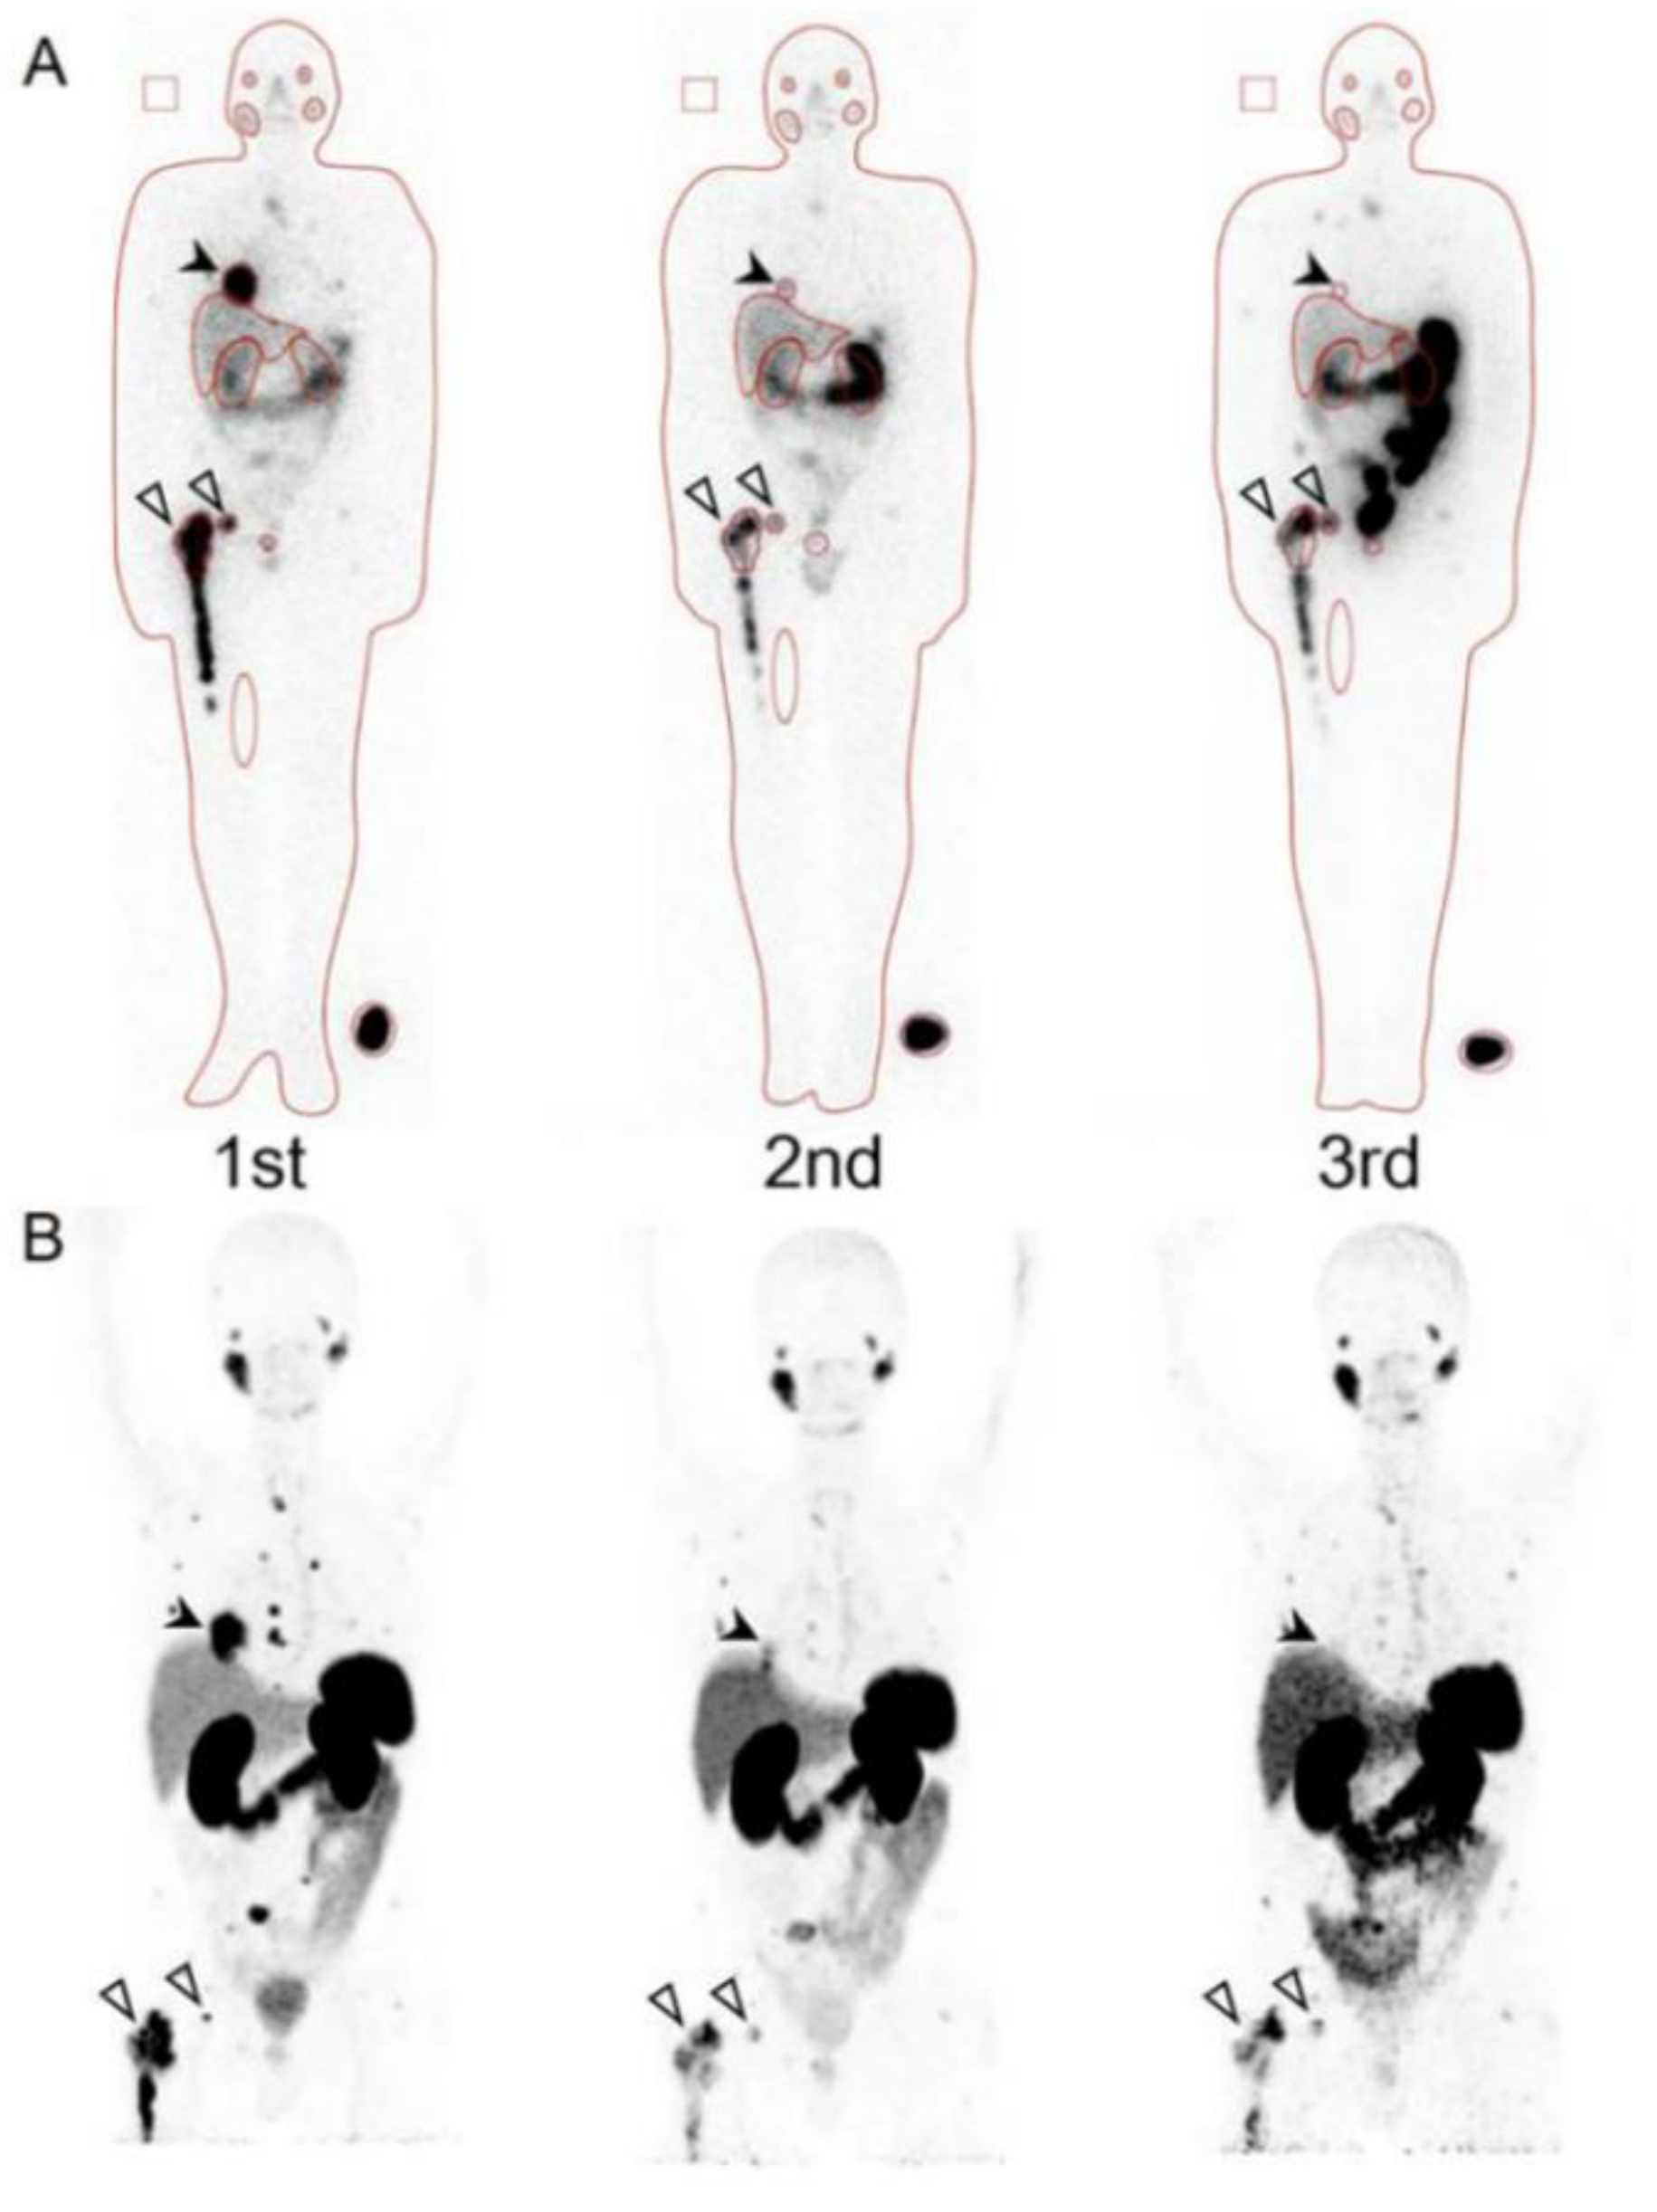

- Yoshinaga, K.; Abe, T.; Okamoto, S.; Uchiyama, Y.; Manabe, O.; Ito, Y.M.; Tamura, N.; Ito, N.; Yoshioka, N.; Washino, K.; et al. Effects of Repeated 131I-meta-iodobenzylguanidine Radiotherapy on Tumor Size and Tumor Metabolic Activities in Patients with Metastatic Neuroendocrine Tumors. J. Nucl. Med. 2020. Online ahead of print. [Google Scholar] [CrossRef]